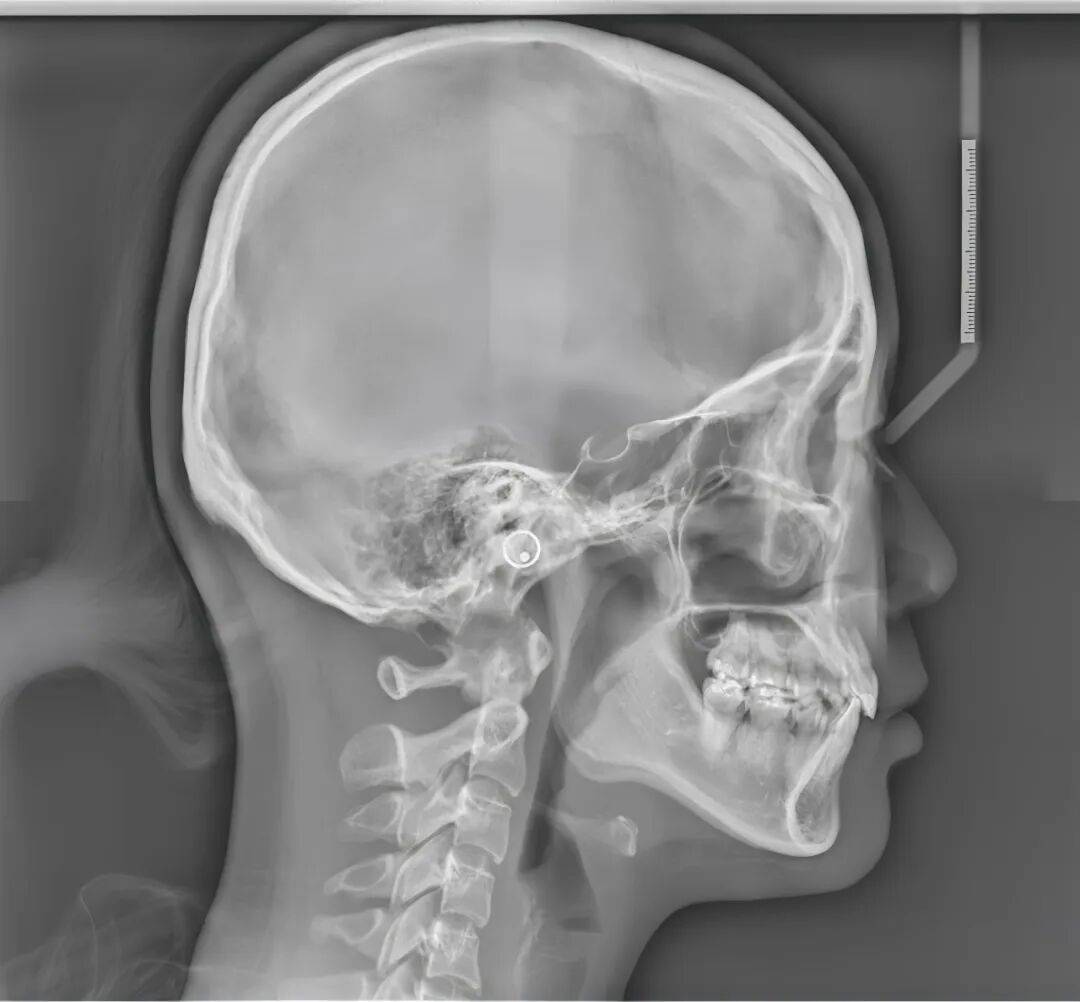

侧貌“标准照”:头颅侧位片 (Cephalometric Radiograph)

这是正畸常用的侧面影像。它同样是二维的,但聚焦于你的头颅侧面轮廓,是正畸医生手中不可或缺的“诊断地图”。

医生在侧位片上进行各种角度和距离的测量,堪比做几何题。

主要用途:正畸诊断与方案设计。医生用它来分析你的上下颌骨关系、牙齿的倾斜度、嘴唇的突度等,为“要不要拔牙”、“牙齿怎么移”这些关键决策提供精确的数据支持。